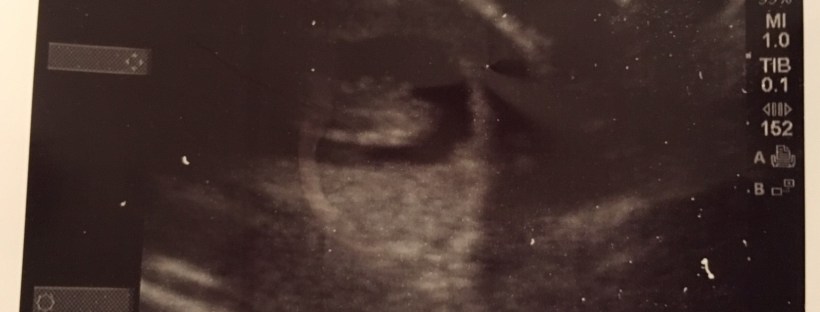

The up side to all of this is last week we had our first ultrasound appointment! They gave us sooooo much information on babies that it was definitely a bit nerve wrecking, told us about potential hazards and diseases, tested my blood, and reviewed my body stats. Apparently – I’m immune to German measles (who knew), am the perfect weight for my height, and have one super active baby with an extremely strong heart beat! The baby was moving around so much they couldn’t get a good measure of it, so I have to get another ultrasound tomorrow to make sure I really am 11 1/2 weeks along. Let’s hope I am because the nausea is supposed to subside around week 12 or 13 and the fact that I’m almost there is brightening my days.

*I think the baby looks like a tiny dinosaur blob. Brice just thinks blob*